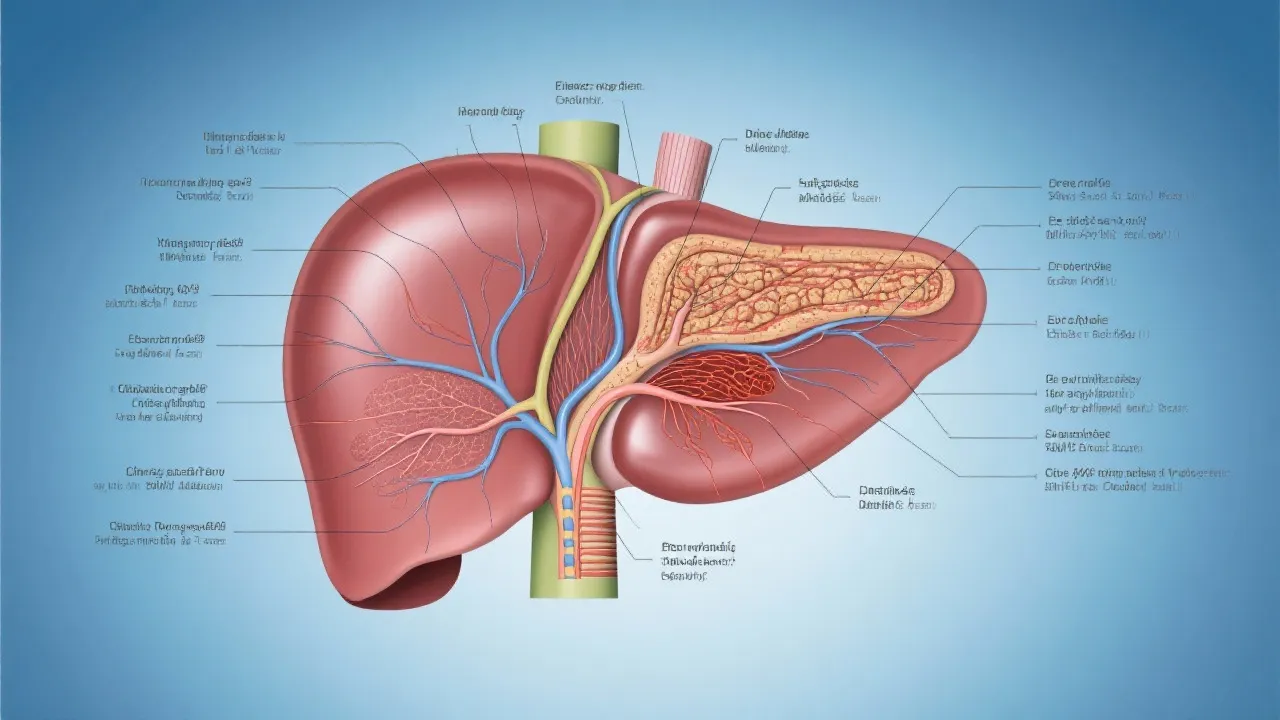

Liver transplantation is a critical medical procedure for patients suffering from severe liver diseases, such as Nonalcoholic Steatohepatitis (NASH). NASH, a form of nonalcoholic fatty liver disease, is distinguished by liver inflammation and can escalate to cirrhosis or liver failure, necessitating a transplant. Moreover, due to rising obesity rates, NASH has emerged as a leading cause of liver transplantation.

Liver transplantation has become a cornerstone treatment for patients with end-stage liver disease due to Nonalcoholic Steatohepatitis (NASH). As obesity and metabolic syndrome rates continue to rise globally, NASH is increasingly becoming a primary reason for the need for liver transplants. The procedure involves replacing the diseased liver with a healthy donor liver, offering a second chance at life for those suffering from severe liver complications. This innovative medical procedure not only addresses the immediate life-threatening situation of liver failure but also opens up avenues for improved quality of life—the latter often being a key consideration for patients aspiring for a normal lifestyle post-transplant.

The liver transplantation process for patients suffering from NASH involves several meticulous steps, starting from a thorough evaluation to post-operative care to ensure the best possible outcomes for these individuals. The whole process is a collaboration between highly specialized medical teams, advanced technology, and the overarching goal of the patient's long-term recovery and health maintenance.

The transplant surgery itself is an intricate procedure lasting several hours. During the operation, the diseased liver is removed, and the healthy donor liver is sutured into place. Careful reconnection of blood vessels and bile ducts is critical to ensure proper liver function post-transplant. The surgery requires the expertise of a multidisciplinary team, including transplant surgeons, anesthesiologists, and surgical nurses. The choice of surgical technique, whether orthotopic (placing the donor liver in the original position) or heterotopic (placing it in a different location), depends on the specific circumstances of the patient, including the anatomy of the recipient and the condition of the existing liver.